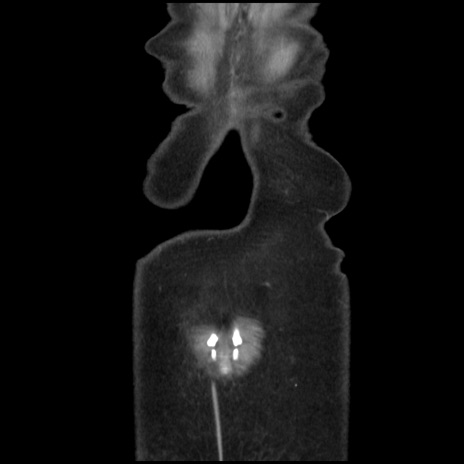

矢状断像

【症例】40歳代 女性

【主訴】上腹部痛、嘔気・嘔吐

【現病歴】約9時間前頃から急に上腹部痛、嘔気、嘔吐が出現。改善しないため救急要請。

【既往歴】子宮頚癌(広汎子宮全摘術、放射線療法)、腸閉塞

【身体所見】腹部:平坦、軟、腸雑音亢進、上腹部を中心に腹部全体に圧痛あり。

【データ】WBC 8400、CRP 0.03